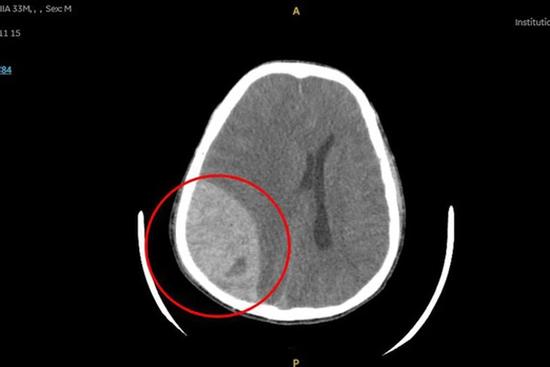

Hy hữu: Người đàn ông bị xuất huyết não sau khi đi bơi

Anh T.M.N - 33 tuổi, ngụ Tây Ninh - cảm thấy nhức đầu sau khi đi bơi, sau đó hôn mê sâu, giãn đồng tử, xuất huyết não dẫn đến nguy kịch.